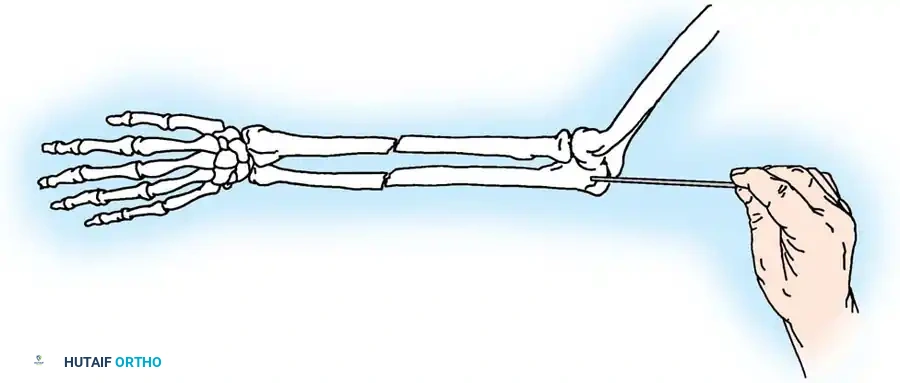

2. Intramedullary Fixation with Tension Band

If the fracture is more distal, or if there is a tendency for the proximal fragment to angulate posteriorly, a simple tension band wire is insufficiently stable. In these cases, intramedullary fixation (using Kirschner wires or a large cancellous screw) is combined with the tension band.

Kirschner Wires vs. Cancellous Screws:

* K-wires: The AO technique utilizes two parallel K-wires (1.6 mm or 2.0 mm) driven down the medullary canal. To prevent proximal migration, the K-wires must engage the anterior cortex of the ulna distal to the coronoid.

* Cancellous Screw: A biomechanical analysis by Murphy et al. demonstrated that a long 6.5-mm or 7.3-mm AO cancellous screw combined with a figure-of-eight wire provides a significantly stronger construct than K-wires. The screw must be long enough to achieve secure purchase in the ulnar diaphysis.

Fig. 54-55 Olecranon fracture repaired with long 6.5-mm AO cancellous screw and figure-of-eight tension band wire loop. Screw must engage cortex of diaphysis of ulna.

🔪 Surgical Technique: K-Wire and Tension Band (AO Technique)

- Reduction: Anatomically reduce the fragments and hold them temporarily with a reduction clamp.

- K-Wire Insertion: Introduce two parallel K-wires longitudinally from the tip of the olecranon across the fracture site. Direct them slightly anteriorly so they engage the anterior ulnar cortex distal to the coronoid process.

- Wire Loop: Pass an 18-gauge wire through a transverse drill hole in the distal fragment. Cross the wire in a figure-of-eight fashion over the posterior surface.

- Proximal Capture: Pass the wire around the protruding proximal ends of the K-wires.

- Double Twist: Weber and Vasey suggest twisting both limbs of the figure-of-eight loop. This double-twist modification ensures uniform compression across the fracture site.

- Securing K-wires: Bend the proximal ends of the K-wires 180 degrees, cut them short, and tap the bent ends deep into the triceps insertion and proximal bone to prevent symptomatic hardware prominence and migration.

Fig. 54-56 A and B, Transverse olecranon fracture repaired with Kirschner wires and tension band technique. C, Double twist modification of wiring suggested by Weber and Vasey.